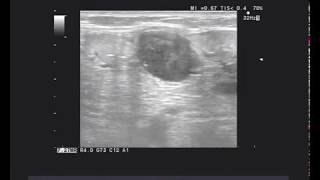

Мастер-класс по радикальной простатэктомии

Преимущества 3D технологии при проведении радикальной простатэктомии

Сергей Валерьевич Попов (Санкт-Петербург) Онкоурология. Лечение локализованного рака предстательной железы низкого и промежуточного риска ...